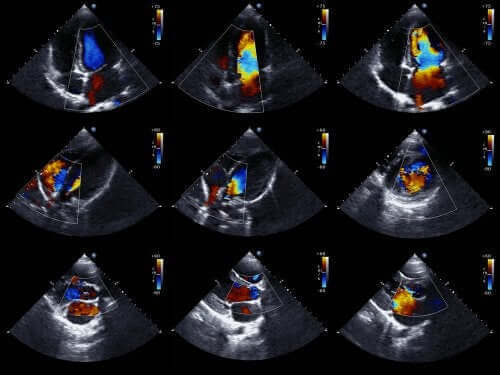

Leger kan vanligvis diagnostisere denne typen avvik før en baby blir født. For å gjøre det bruker de ekkokardiografi for fostre. Dette er en teknikk som bruker lydbølger for å gjenskape et bevegelig hjertebilde.

Takket være dette kan vi se utseendet på hjertet og undersøke hvordan det fungerer når en baby fortsatt er i livmoren. Med denne informasjonen kan leger behandle problemet umiddelbart etter fødselen.